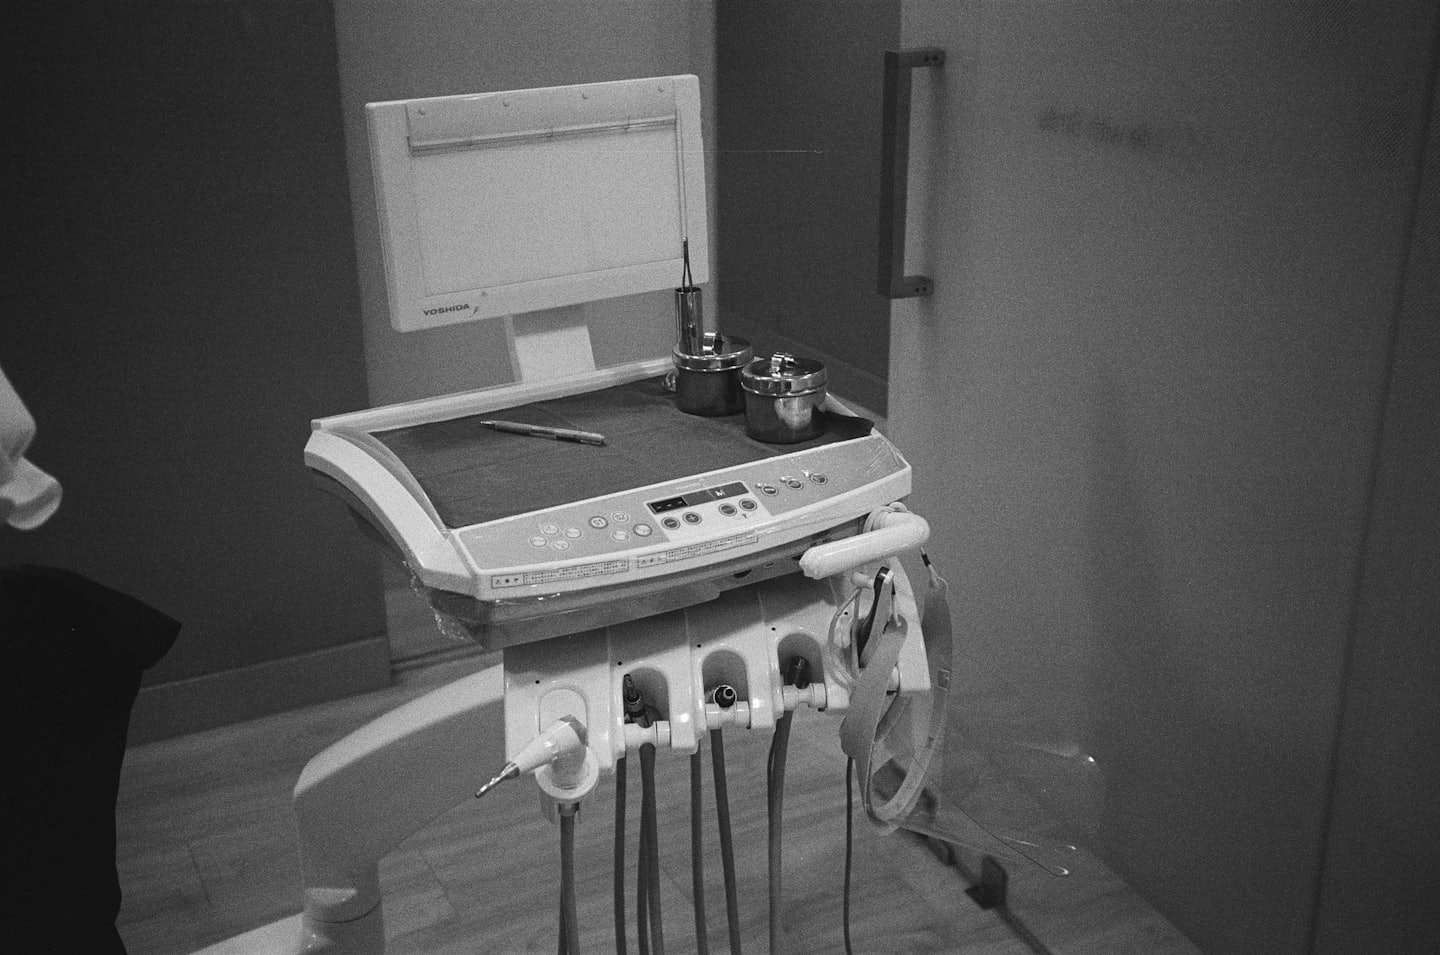

Tecnología avanzada

Utilizamos equipos modernos para diagnósticos precisos y tratamientos efectivos